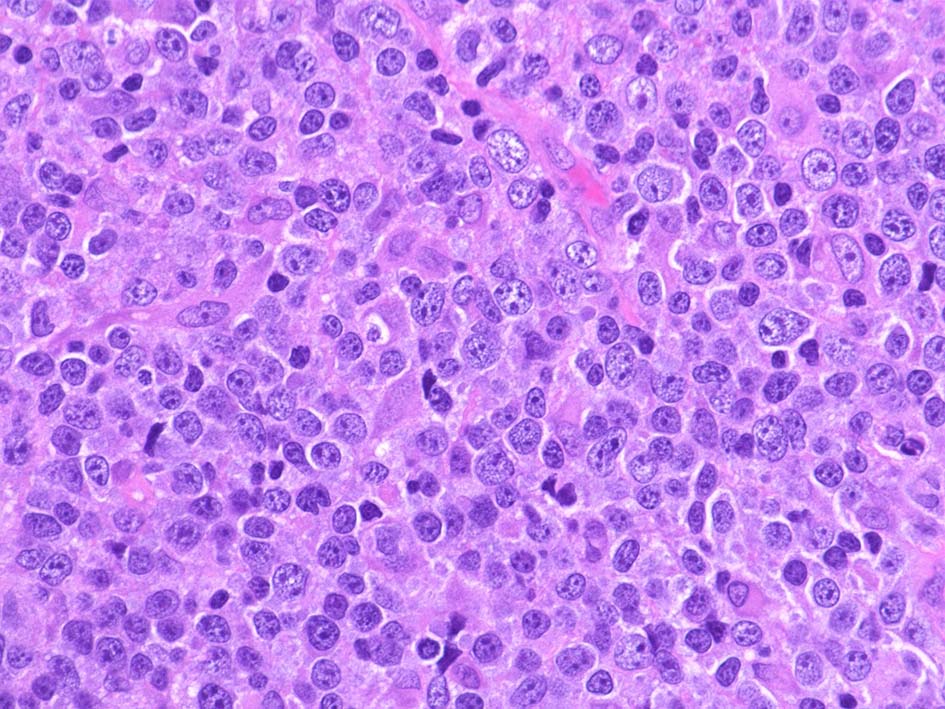

Diffuse large B-cell lymphoma(DLBCL) びまん性大型B細胞リンパ腫

大細胞の定義は, 組織内に存在する小リンパ球とくらべて2倍以上の大きさ (以前はいろんな細胞;内皮や組織球など,と比べる説があったが今はこれ小リンパ球)

Centroblastic variant(胚中心芽球型)

• 最も多くみられるtype.腫瘍細胞は胚中心, centroblastに似る. (核膜に付着するように核小体が2~4個認められる)

• 核はほぼ均一な大きさのことが多いが, ときに大小不同がめだつこともある.まれに分葉ないし多核に見える細胞が混在.

免疫芽球が混在することもある.

• 分葉構造がめだつことがあり, 節外性に多い. GCBが多い.